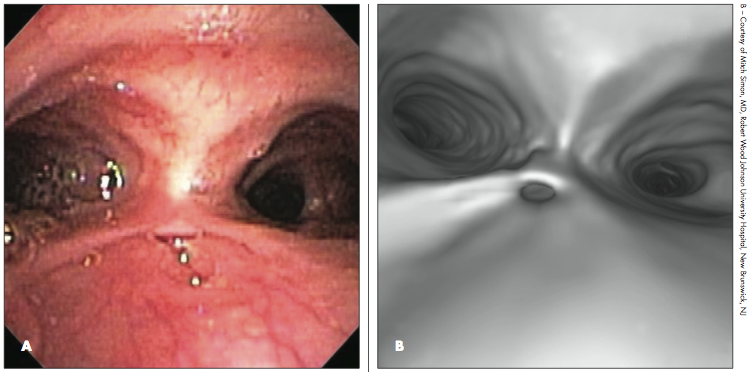

Diagnostic evaluation included an esophagram with a catheter, which demonstrated no stricture, anastomotic leak, or recurrent TEF. Flexible bronchoscopy revealed tracheomalacia and secretions bubbling out of a diverticulum in the posterior tracheal wall at the repair site (A).This finding was confirmed by a 3-dimensional CT scan of the chest (B).

Tracheal diverticulum as a complication of TEF repair has been reported.5 The diverticulum contributes to poor airway clearance and increased risk for recurrent pneumonia and atelectasis by several possible mechanisms, such as obstructing lower airway clearance and facilitating the pooling of secretions from the proximal airway.

Excision of the diverticulum has been shown to reduce symptoms.5 This patient’s diverticulum was obliterated with cauterization, and her respiratory symptoms subsequently resolved with no documented pneumonias.